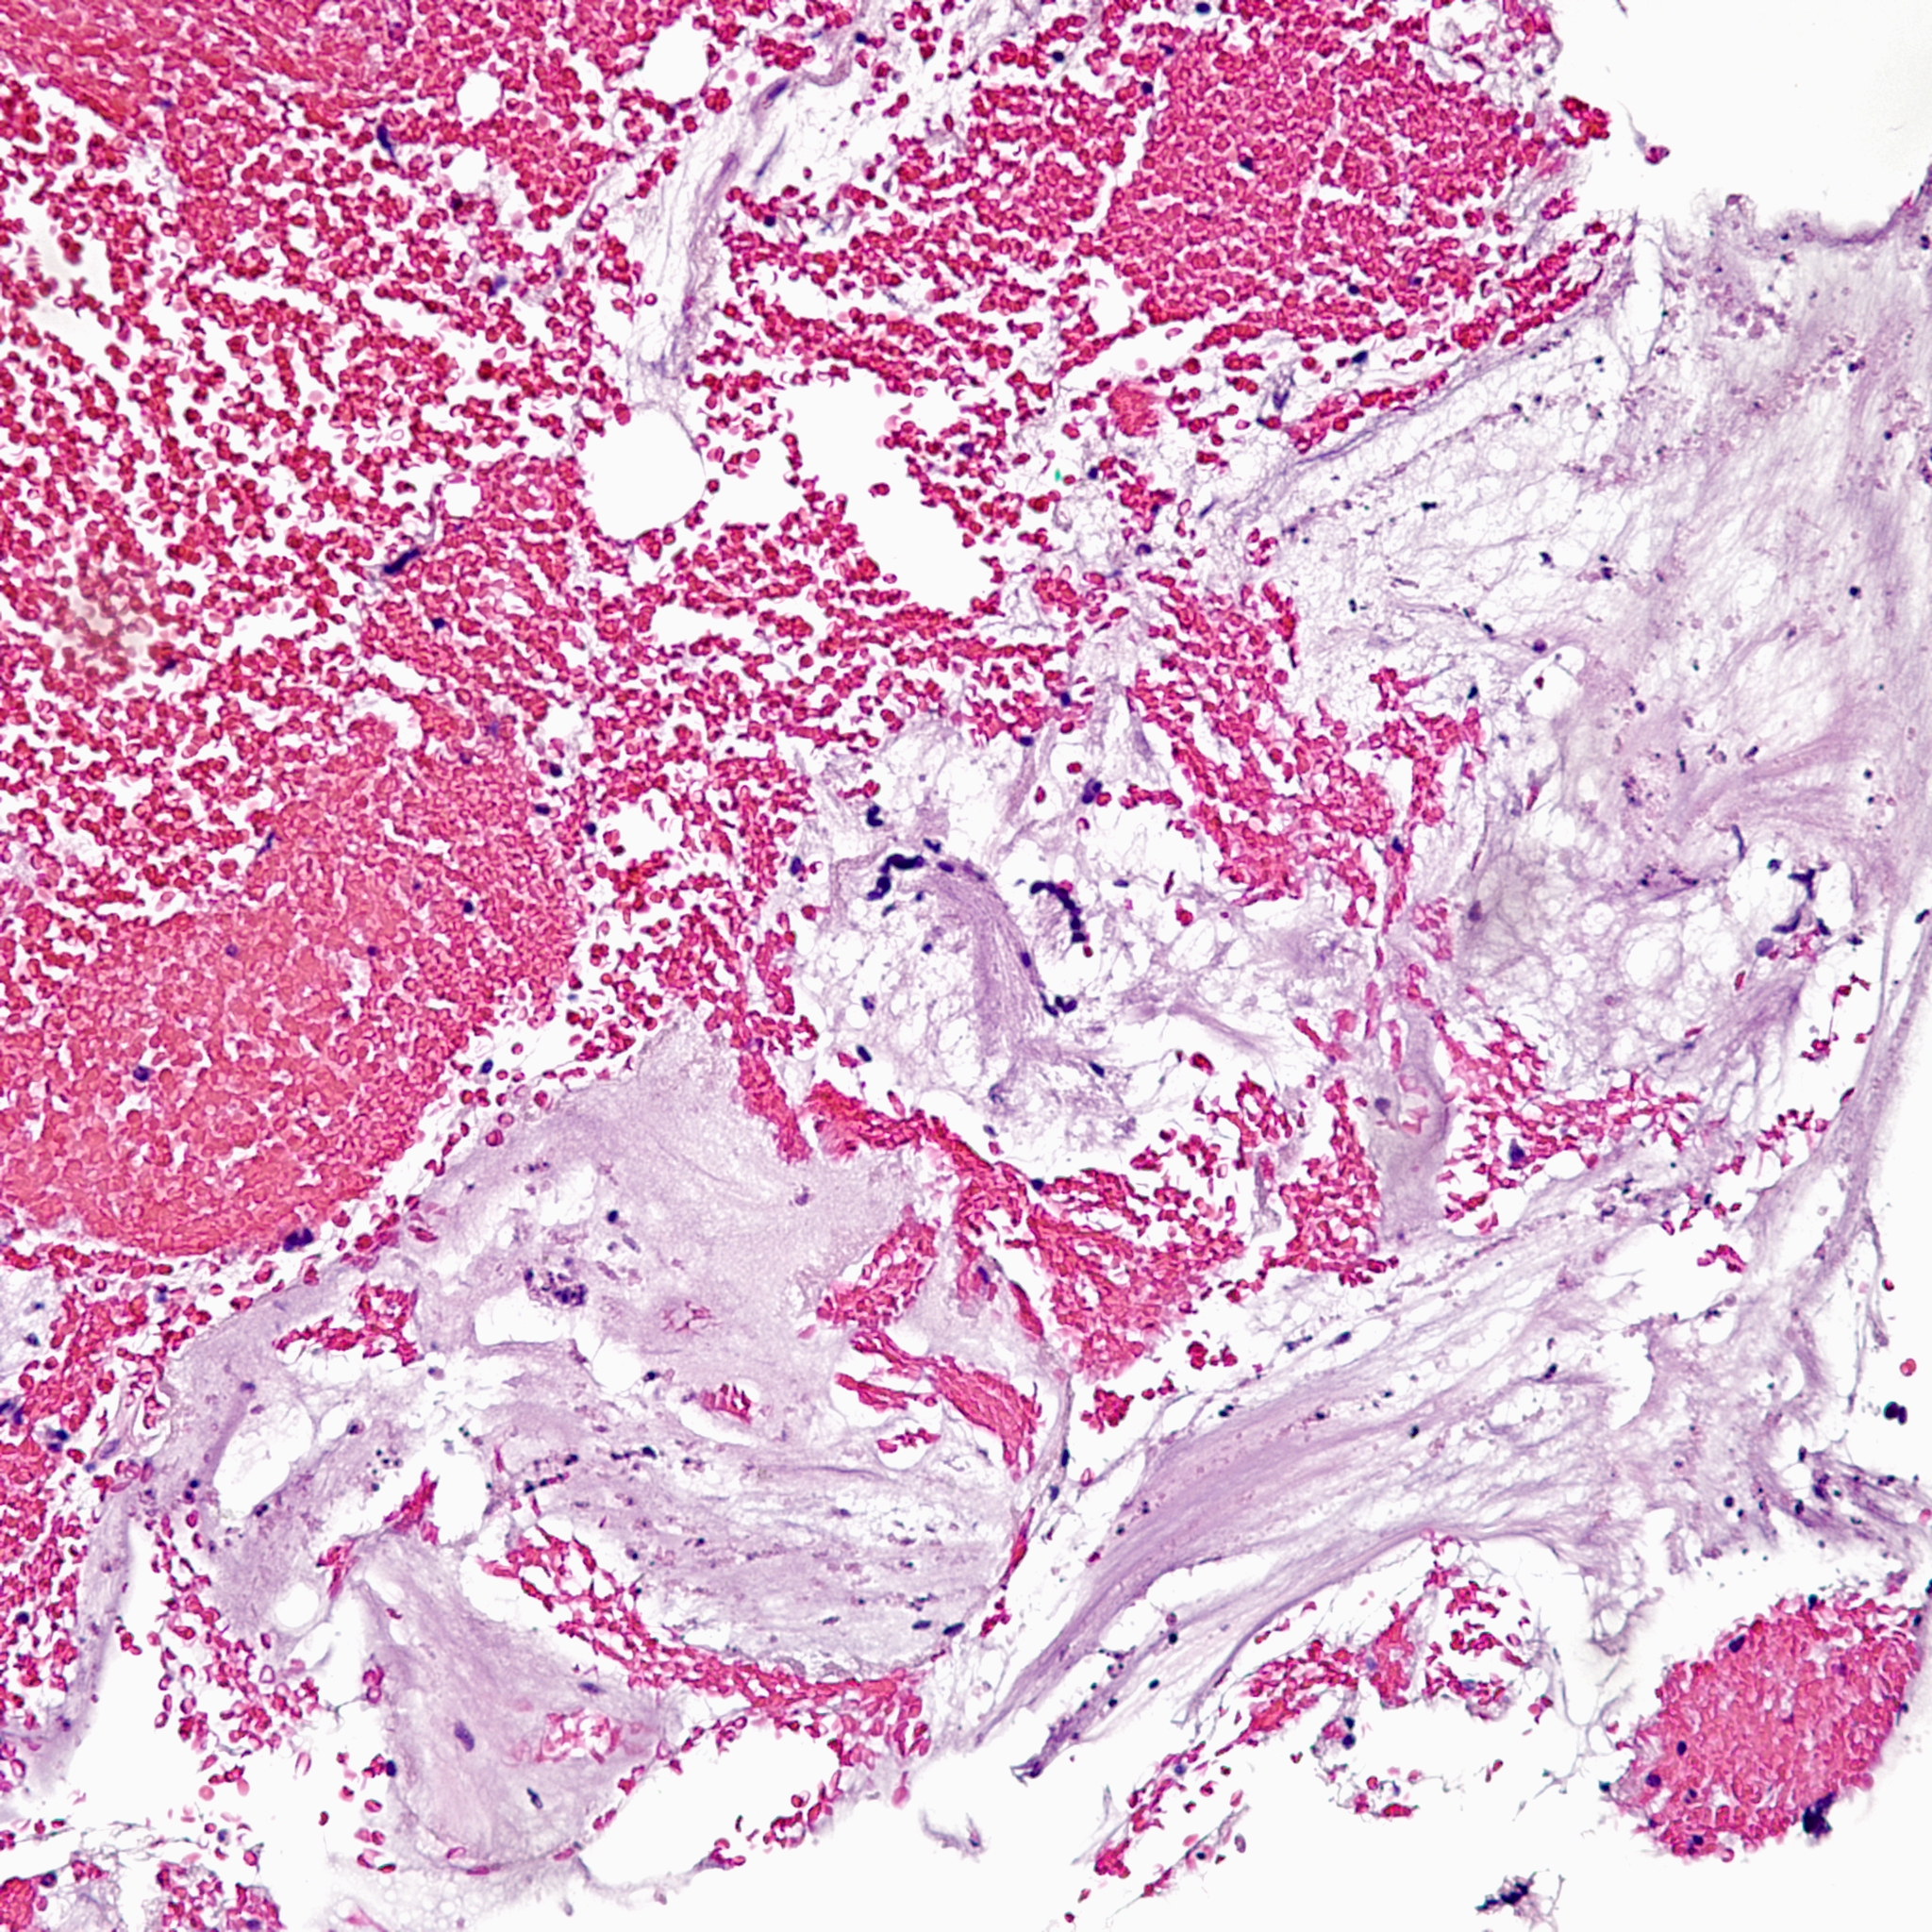

However, in one field we see a well-circumscribed nodule that, on low power, is very pink and glassy appearing, with large cells admixed.